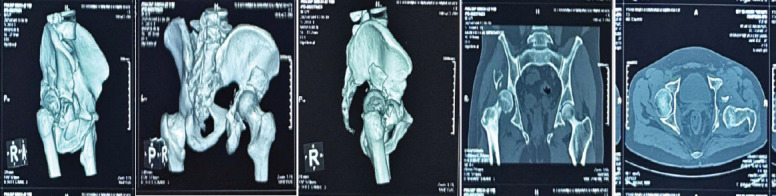

Case report: We report a case of a 42-year-old male with a chronic posterior dislocation of the right hip and a comminuted posterior wall and column acetabular fracture, presenting 2 months post-injury. The patient had previously undergone a right-sided patellectomy. Surgical intervention included THA with acetabular cage reconstruction due to segmental bone loss. At 6-month follow-up, the patient achieved pain-free ambulation, a stable prosthesis, and satisfactory functional outcomes.